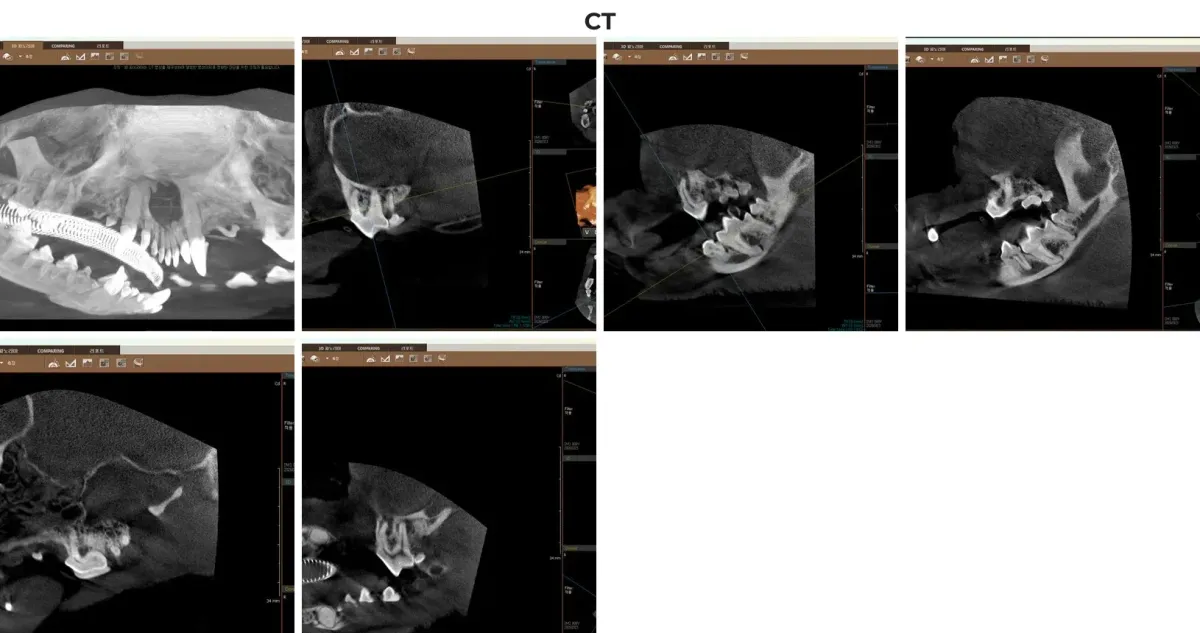

ℹ️ 치과 CT의 중요성: 육안으로 안 보이는 치근 병변 확인

크롱이처럼 이미 다수의 치아가 빠지고 남은 치아 주변의 뼈가 심하게 녹아내린 경우, 2D 일반 엑스레이만으로는 턱뼈의 두께나 신경관과의 거리를 정확히 파악하기 어렵습니다. 광주·전남 유일의 동물 치과 전용 CT를 촬영함으로써, 108번 치아 뿌리 끝의 숨은 염증(PA3) 낭종 크기와 턱뼈 골절 위험도를 3D 입체 영상으로 0.1mm 단위까지 정확하게 평가할 수 있었습니다. 이는 수술 중 발생할 수 있는 합병증을 완벽에 가깝게 차단하는 핵심 과정입니다.

광주 전남 유일 동물전용 치과 CT로 촬영한 크롱이의 3D 턱뼈 및 치조골 흡수 입체 분석 영상